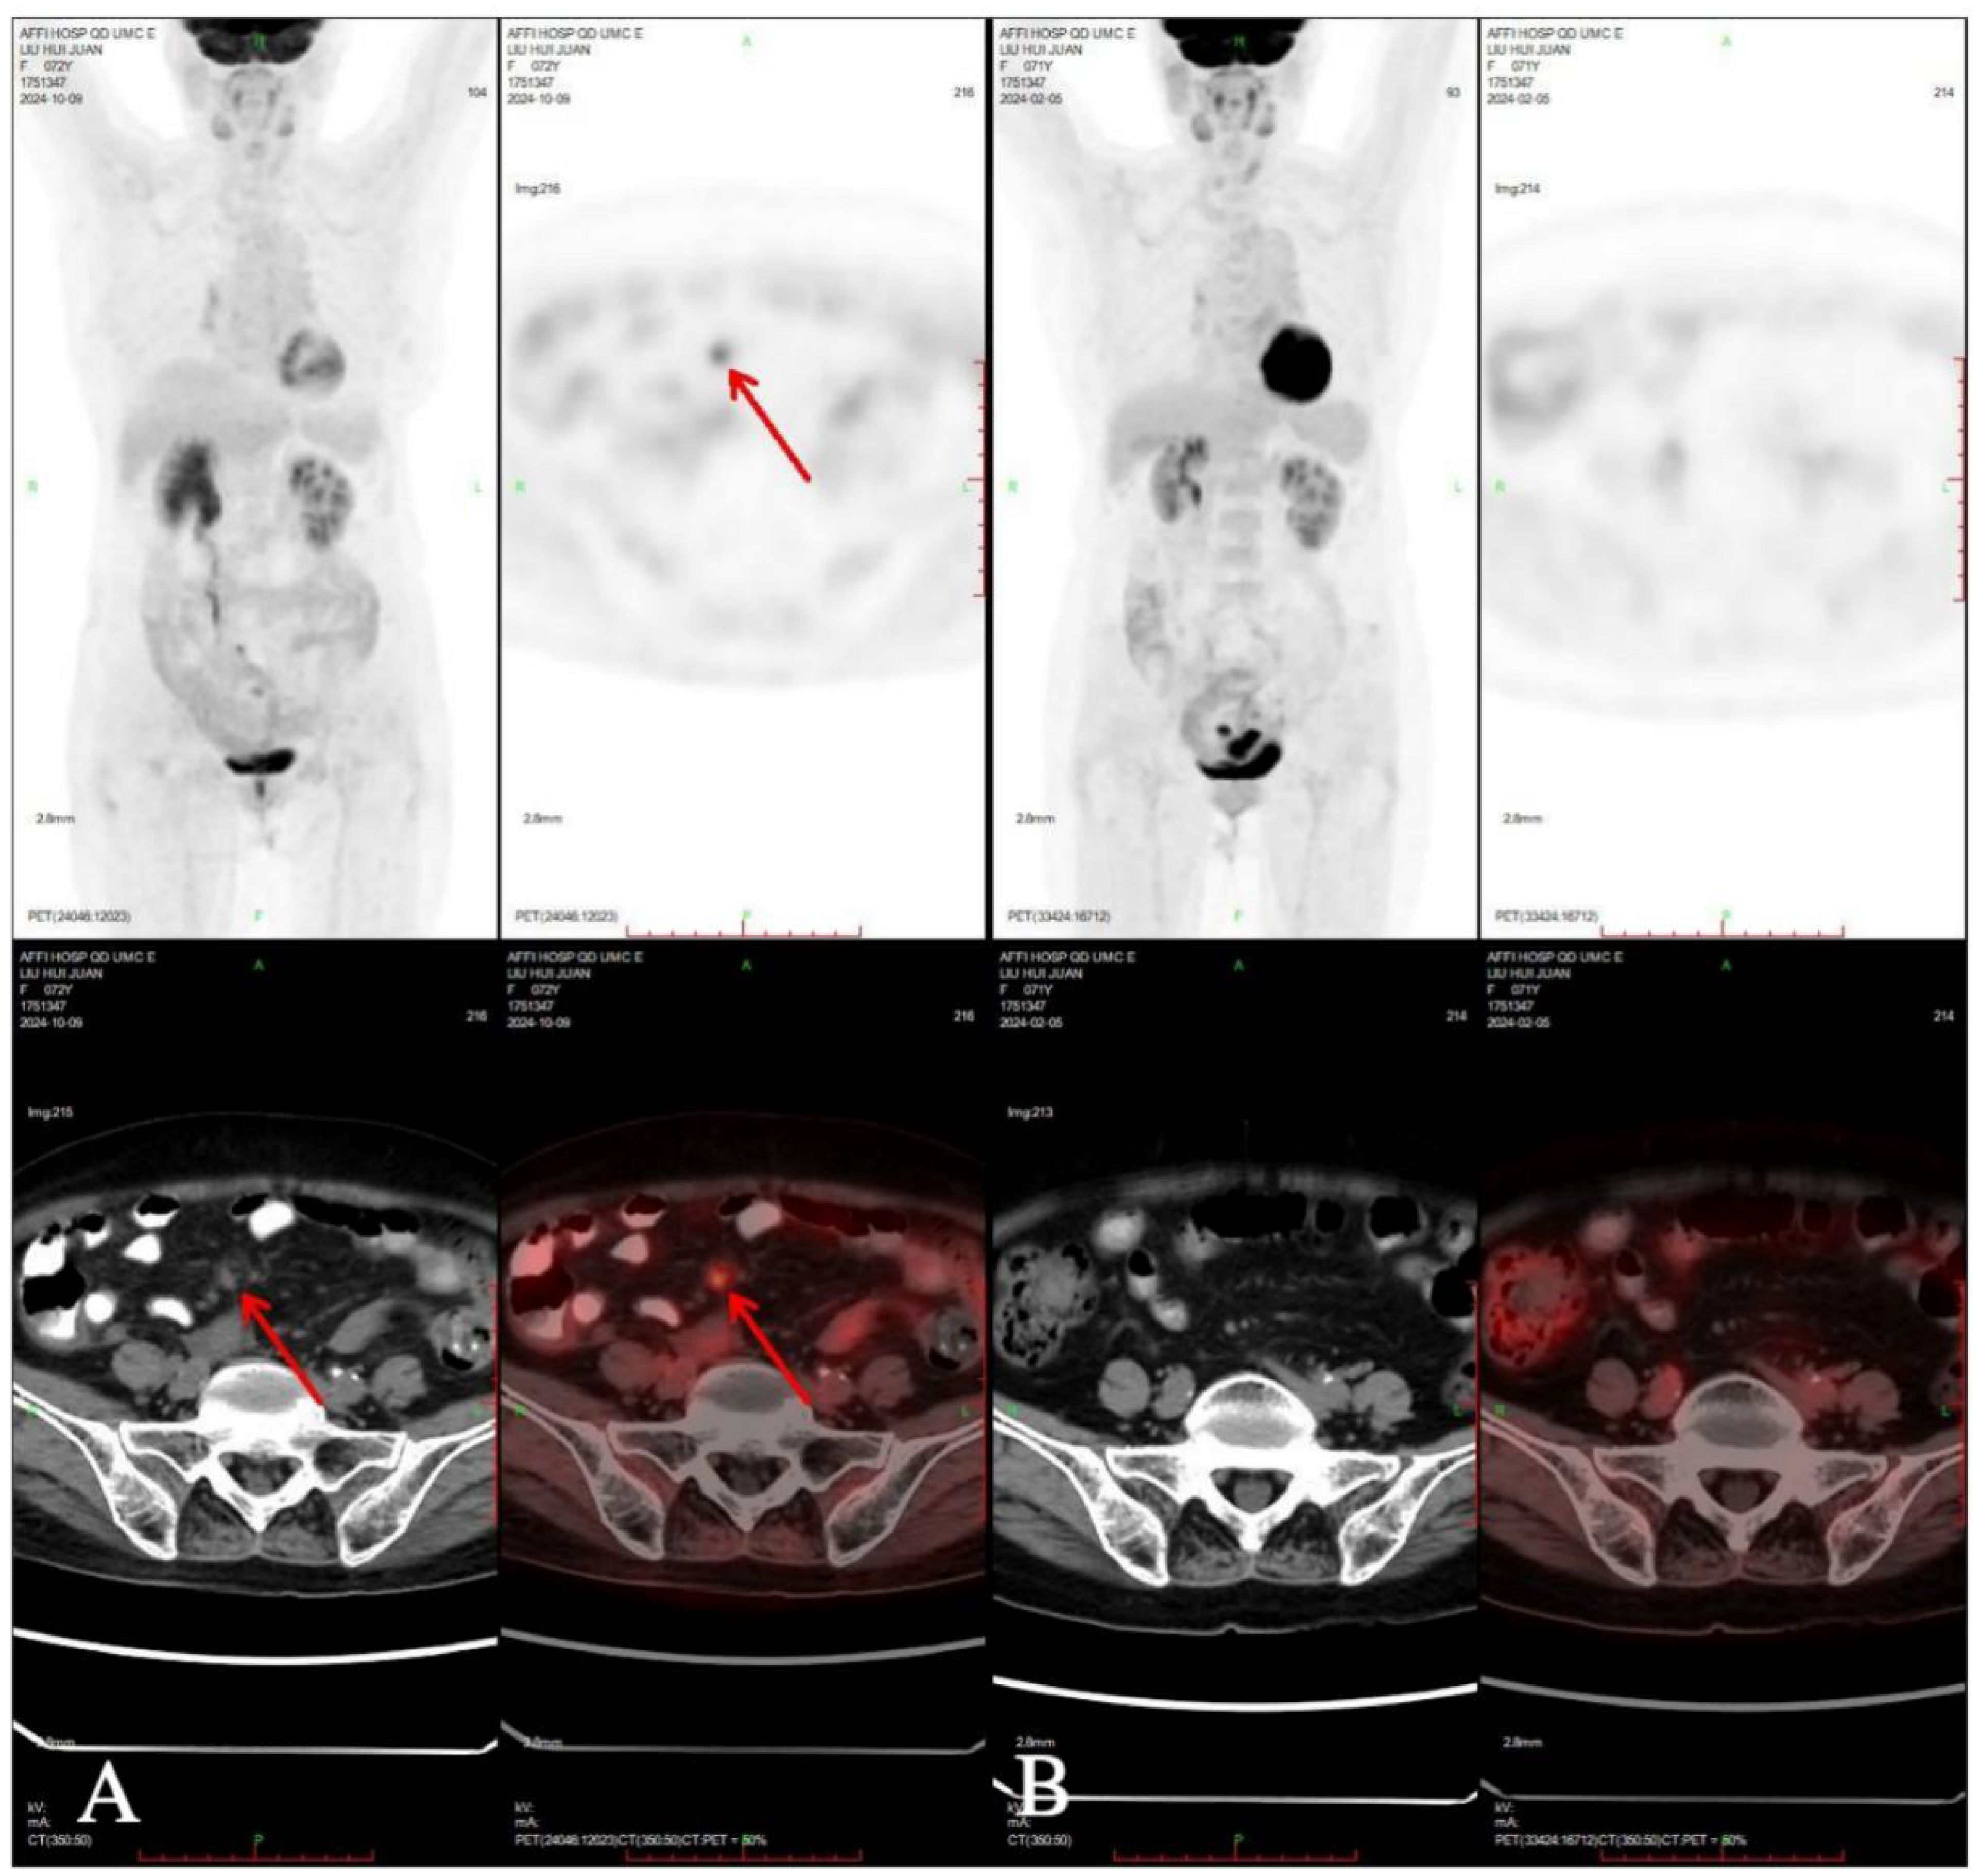

One month after chemotherapy, the patient developed dysuria. Ultrasound showed right hydronephrosis, and CT suggested possible metastatic nodules in the left pelvic peritoneum. PET/CT revealed a new hypermetabolic soft-tissue lesion (SUVmax ≈4.3) in the mesentery (Figure 5), indicating recurrence. Serum AFP was measured at 3.16 ng/mL (reference range 0–7 ng/mL). Given these examination results, the possibility of metastasis and recurrence was considered. The patient requested continued observation without treatment. On April 7, 2025, chest CT detected multiple pulmonary nodules suggestive of metastasis (Figure 6), though AFP remained normal. Multidisciplinary consultation recommended paclitaxel (240 mg/m²) + carboplatin (AUC = 5) + pembrolizumab (2 mg/kg).

Figure 5. Compared PET-CT (A) in 2024-10-09 with PET-CT (B) in 2024-02-05, new lesions were found in the omentum.